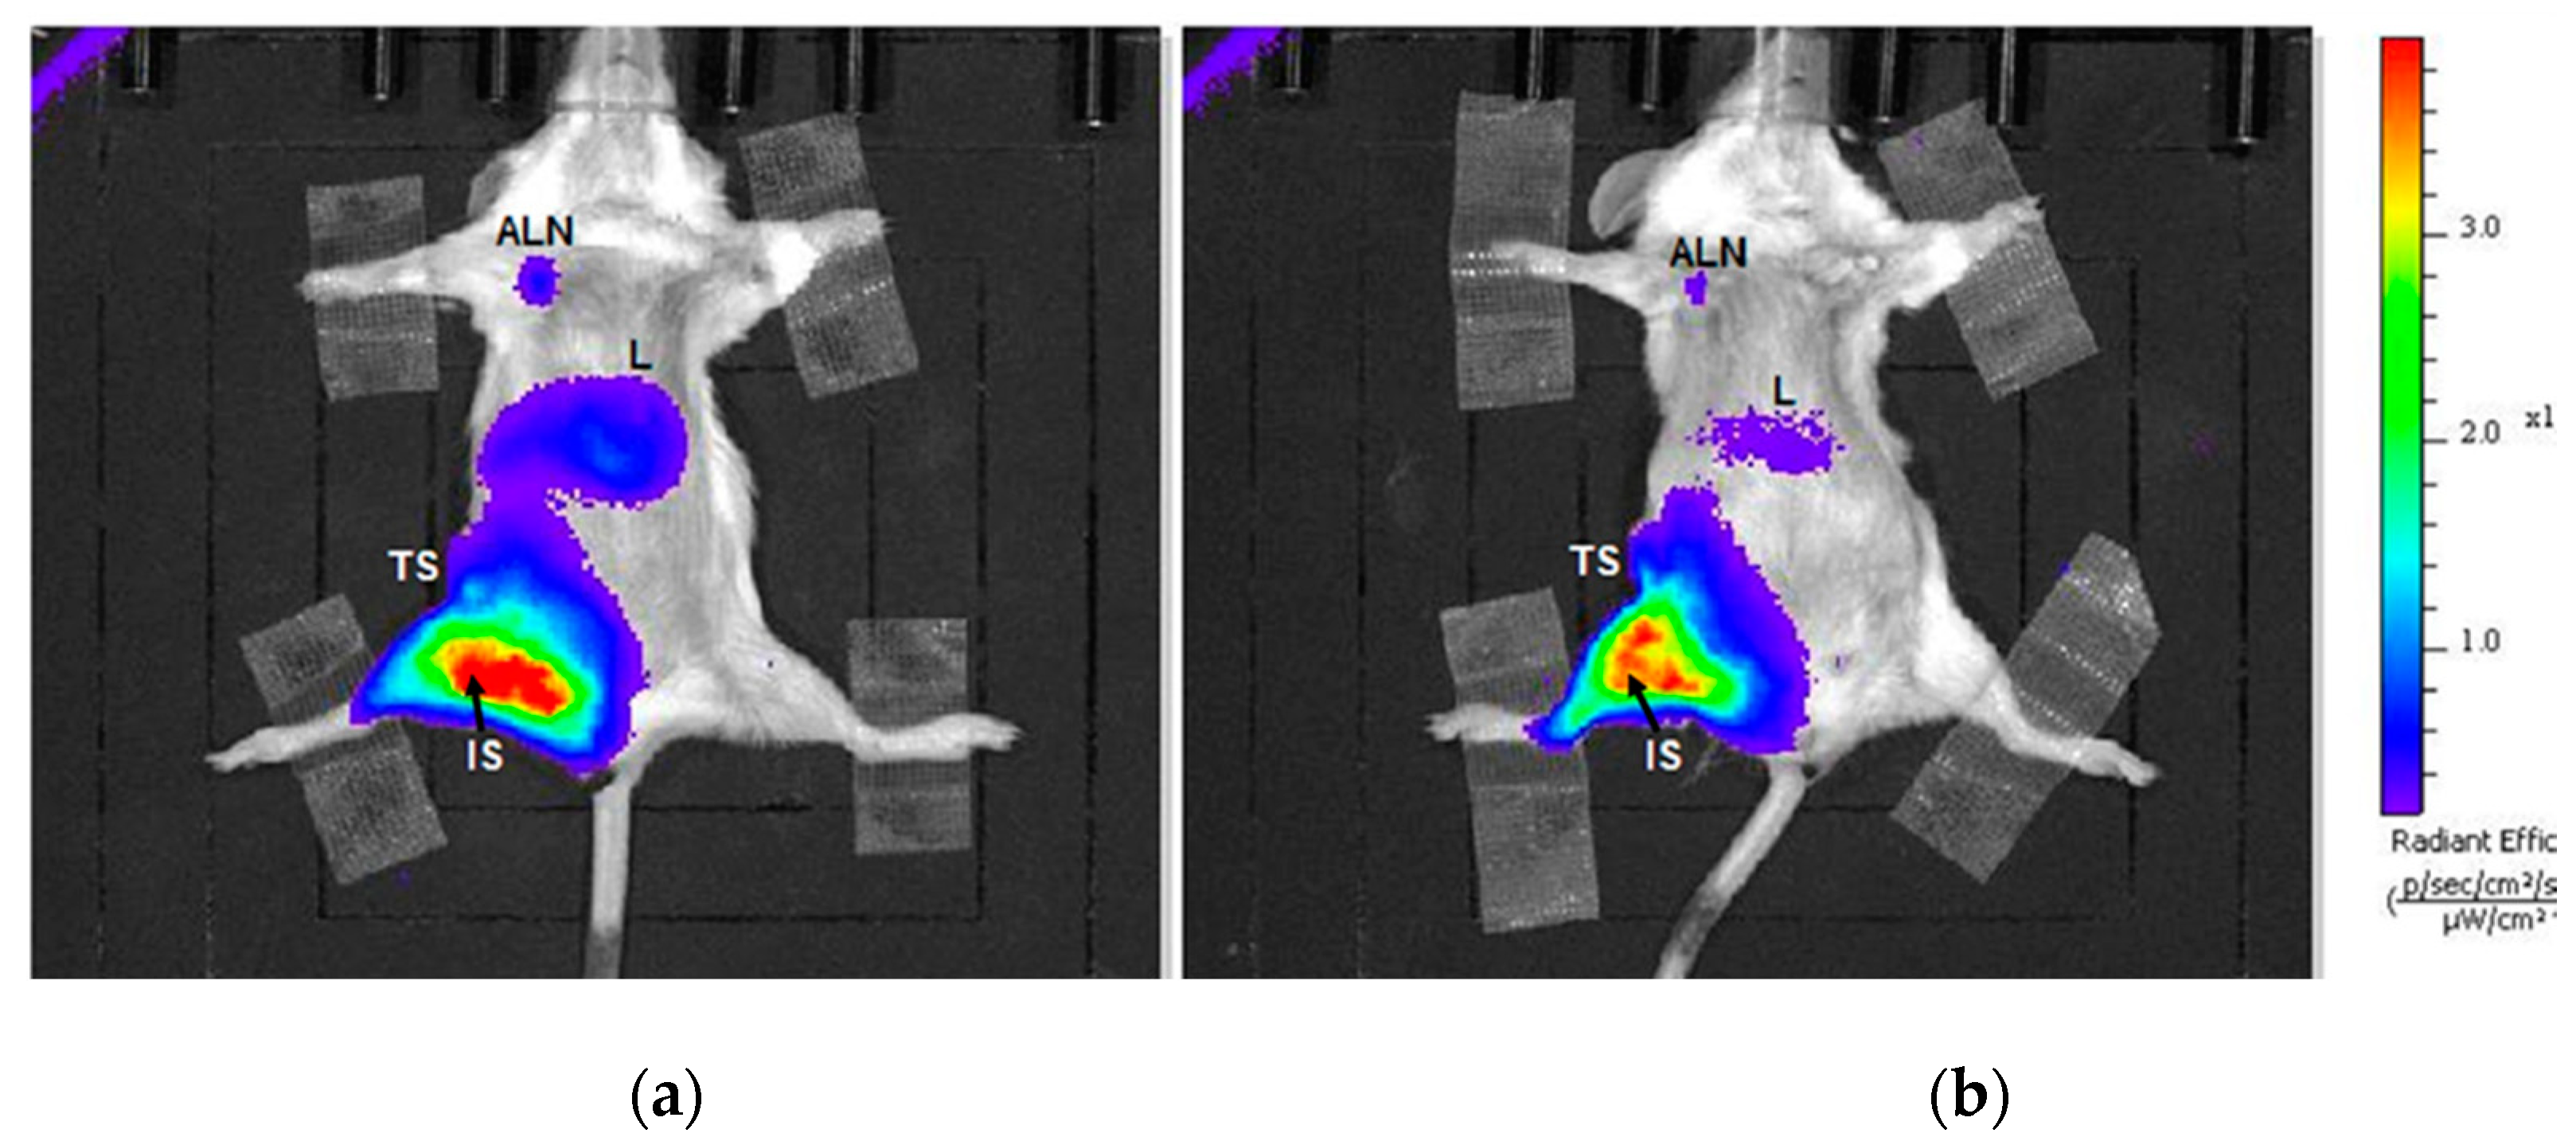

Figure 2.

Representative images of in vivo fluorescence from (a) MN and (b) MNOX group. Fluorescent signals from axillary lymph nodes (ALN), livers (L), tumor sites (TS) and injection sites (IS). Images show mice three days after intramuscular injection of (a) MN or (b) MNOX.

According to in vivo fluorescence optical imaging of the MN and MNOX groups (Figure 2), the highest signal issued from the inguinal lymph node next to the tumor and injection site (SLN) (Figure 3a, Figure S4a). The signal reached its maximum in both groups between the 4 and 24hours after injection of MN or MNOX, one order of magnitude higher in the case of MN-DOTA Gd-IR800 (as with all other in vivo fluorescent signals). The second highest fluorescent signal measured originated from the liver (Figure 3e, Figure S4e), peaking at around 24 h after the injection of MN or MNOX and then continuously decreasing. This signal was again higher in the MN group. The DOT group had always a fluorescence signal lower than the background fluorescence signal.

We later detected the signal from the axillary lymph node on the tumor site (Figure 3b, Figure S4b), reaching its maximum 48 h after injection of MNOX (Figure S4b) and 72 h after injection of MN. The lowest fluorescent signal of all the measured lymph nodes issued from the axillary lymph node at a non-tumor site (Figure 3c, Figure S4c). However, the peak fluorescent signal from this lymph node was recorded only 2 h after administration of the contrast agent, a relatively short time span.